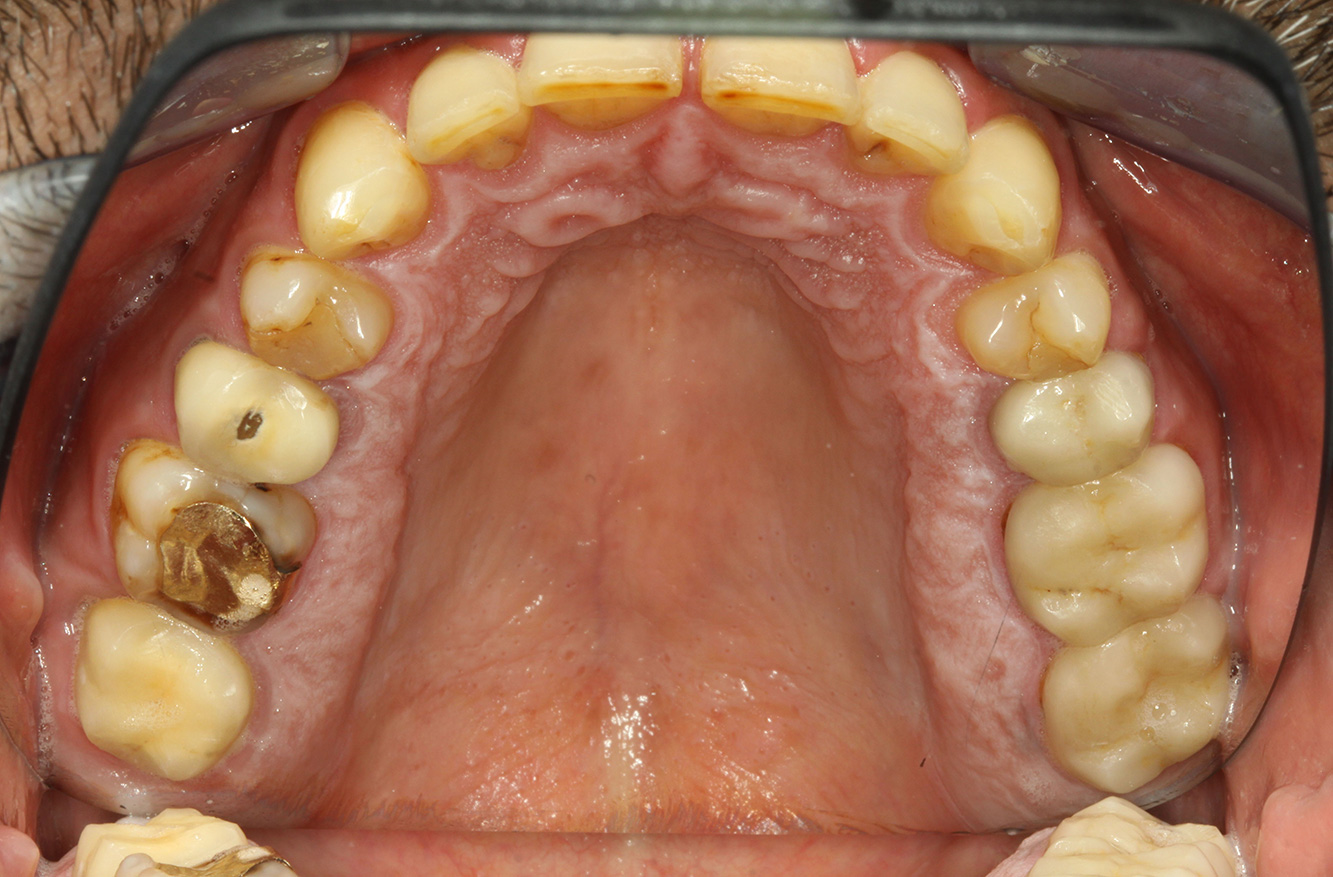

The patient is 39 years old and has previously undergone aortic valve replacement due to valve failure and endocarditis. ASS 100 is taken regularly as an anticoagulant. In terms of lifestyle, the patient’s diet is classified as caries-promoting due to the regular consumption of sugary foods and the fact that six to seven meals are consumed daily. The patient’s oral health indicates a moderate risk of caries, with active lesions. The risk of periodontitis is low, but gingivitis is present. The following recommendations are made for prophylactic treatment.

The heart valve replacement and the history of endocarditis indicate an increased risk of complications. In order to reduce the risk of inflammation recurring, antibiotic prophylaxis is recommended (e.g. 2 g amoxicillin, 1 hour before the session). Despite the long-term blood-thinning medication, it is not expected that there will be an increased risk of bleeding in the prophylactic session.

No specific instrument recommendations can be determined for the prophylaxis session. Targeted application of air and rotary polishing can be used to gently reduce plaque and stains on the restoration edges, and to reduce recolonization niches for cariogenic bacteria (19).

Fluoridation is recommended to further support the prevention of caries, and especially to prevent new formation around thethe restoration edges, and to seal the root surfaces. Both of these measures can reduce the teeth’s sensitivity to temperature.